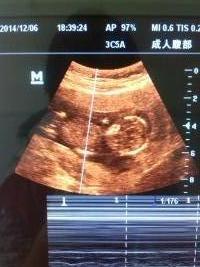

谁能帮忙看B超图片,以下是孕40天与孕13周照的B超图,现在是二胎压力大啊,请帮忙看看吧